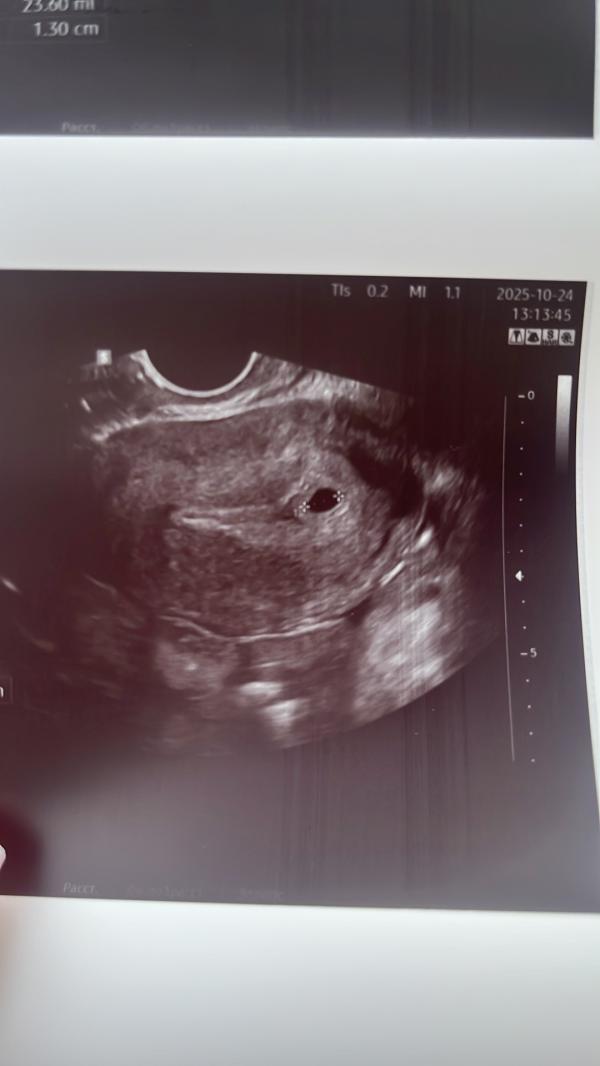

УЗИ на 4-5 неделе беременности: размер ПЯ 7 мм

Хгч я больше не сдавала , крайний раз был 361,подождала 5 дней и пошла на узи …. Вот моя крошка 😍 пя 7 мм , срок 4/5 недель .